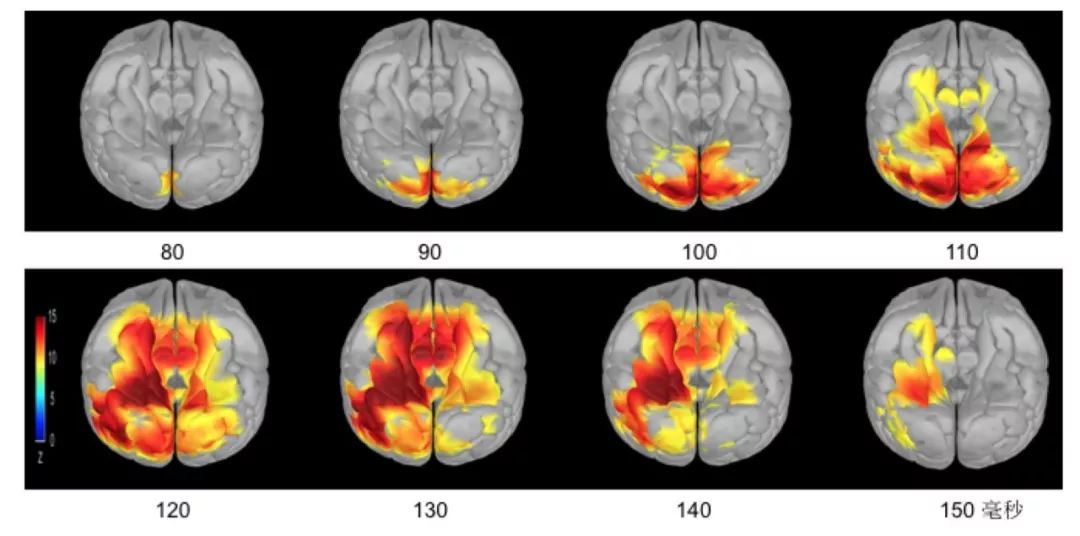

表情识别里,起着重要作用的,名叫腹内侧前额叶的这个脑区,实则在很早的时候,就参与了情绪的粗略加工,大脑前额叶也是如此(见图)。

“恐惧”表情识别大脑腹侧通路的时间序列加工

有关快速表情识别的加工,研究数据向我们表明,腹侧通路十分关键,特别是腹内侧前额叶于情绪价值的大致判断方面所起的作用,为不同脑区回路在表情识别里的作用给出了新的证据。